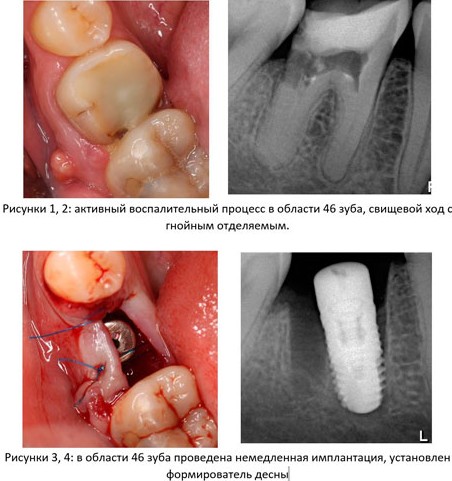

Последнее весьма условно, ибо даже при наличии значительных по размеру кист и гранулем, свищевых ходов с гнойным отделяемым, метод немедленной имплантации вполне себе работает, при условии, что даже возникший из-за воспаления дефицит костной ткани не усложняет установку и позиционирование импланта, — и я это наглядно показал в своей лекции:

Кроме того, у меня есть примеры случаев, когда даже удаление зуба по острой боли не является препятствием для немедленной имплантации, хотя, я повторюсь, к таким случаям следует относиться очень и очень осторожно. И лучше отложить имплантацию до снятия острых воспалительных явлений.